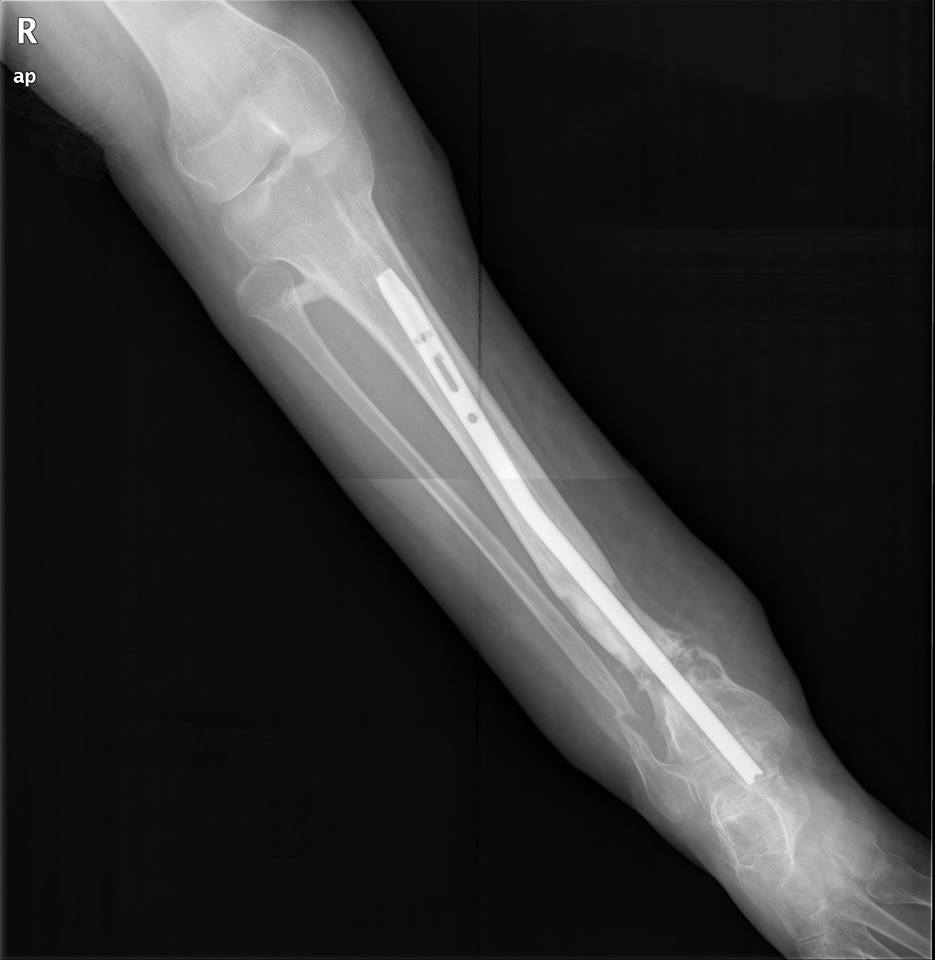

Уважаемые коллеги,Есть девушка с таким вот гвоздиком.

В плане - удаление и реостеосинтез.Вопрос - как минимально инвазивно удалить это чудо? Понимаю, что ранее вопрос поднимался, но тут мне кажется случай не стандартный.Спасибо.

Это UTN (Synthes) или его клон. То есть резьба M6.

Извлекли даже без ожидаемых приключений. Стержень от Илизаровского аппарата in vivo не полез (in vitro позже - как родной), но удалалка от нашего Медбиотеховского стержня зацепилась и все ушло вполне гладко. Спасибо за совет!

Закрыто деформация устранялась, но не полностью (и слегка поперечный компонтент смещения появлялся), поэтому и с учетом анамнеза открыли несращение с декортикацией, устранили деформацию, рассверлили, зафиксировали стержнем потолще и винтов дистально 4 штуки. Костная пластика (вскрывали канал фрезой, получили хороший столбик), шов. Снимки на неделе сделаем.